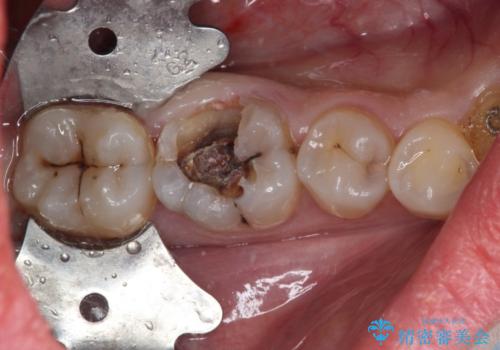

術前の診査では、神経を取り除かなくても済む可能性が示唆されましたが、実際に虫歯除去を進めたところ、レントゲン写真から読み取れる通り、神経組織にまで虫歯が及んでいることが分かりました。

速やかにラバーダム下にて根管治療を行うこととし、その後オールセラミッククラウンにて補綴治療を行うこととしました。